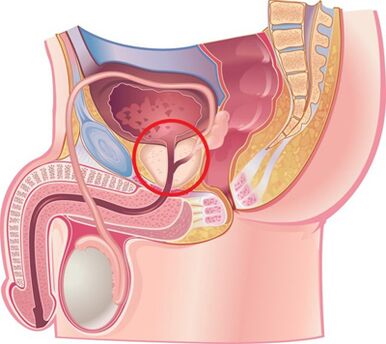

Selon de nombreux experts, la prostatite chronique est une maladie inflammatoire causée par une infection avec éventuellement l'ajout de maladies auto-immunes, caractérisée par des lésions du tissu parenchymateux et interstitiel de l'organe. La médecine connaît cette maladie depuis 1850, mais elle reste encore aujourd’hui peu connue et difficile à traiter. Les prostatites chroniques bactériennes (6 à 10 %) et non bactériennes (80 à 90 %) sont les maladies inflammatoires les plus courantes et socialement significatives chez les hommes et réduisent considérablement leur qualité de vie. La maladie est enregistrée principalement chez les personnes jeunes et d'âge moyen et se complique souvent de troubles des fonctions copulatoires et génératives (diminution de la puissance, infertilité, etc.). La maladie est enregistrée chez les hommes entre 8 et 35 % des cas entre 20 et 40 ans.

La cause de la prostatite bactérienne est la flore pyogène qui pénètre dans la glande par l'urètre ou par les voies lymphogène et hématogène. L'étiologie de la prostatite chronique non bactérienne et sa pathogenèse restent inconnues. Elle touche principalement les hommes de plus de 50 ans.

Selon les experts, le rôle principal dans le développement de la prostatite chronique appartient au reflux urinaire intraprostatique, lorsque l'urine s'écoule de l'urètre vers la glande, ce qui provoque une vidange déficiente des vésicules de la prostate et des séminaux.

Pendant la maladie, des réactions vasculaires sont développées qui provoquent un gonflement de l'organe, le nerf et la régulation humorale du ton du tissu musculaire lisse de l'urètre est modifié et l'activation alpha est activée.1-Les récepteurs adrénergiques provoquent le développement d'une obstruction dynamique et contribuent au développement d'un nouveau reflux intraprostatique.